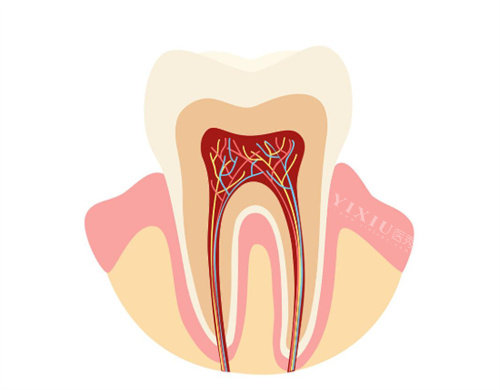

八、根管治疗价格

根管治疗是治疗牙髓病和根尖周病的有效方法,柳州东成口腔的根管治疗项目由经验充足的医生团队操作。